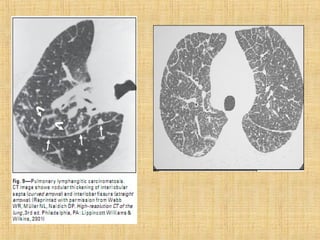

As principais informações do documento são: 1. Discute os padrões de doença pulmonar causados por metástases, incluindo nódulos, espessamento intersticial e obstrução das vias aéreas. 2. A prevalência de metástases pulmonares varia de 30-55% dependendo do tumor primário, e são mais comuns em pacientes acima de 50 anos. 3. Os achados clínicos mais comuns são dispneia, hemoptise e febre, enquanto exames de escarro ou lavado brô